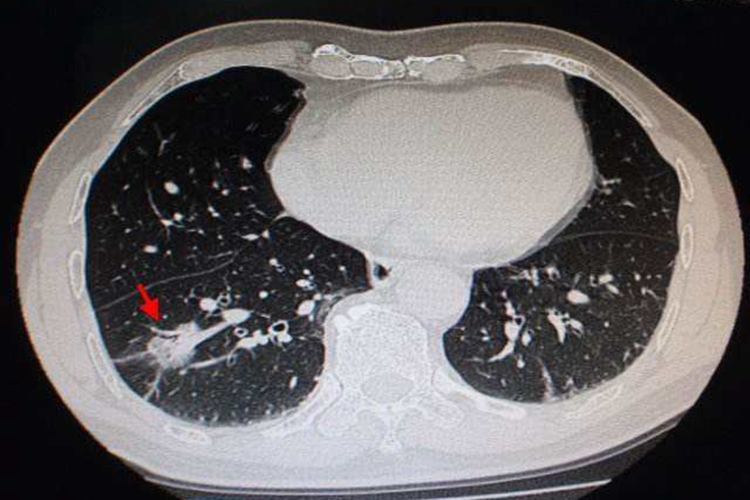

早期肺部恶性肿瘤往往无症状,随着肿瘤进展,可出现咳嗽、血痰、胸痛、发热、气促等症状。影像学检查主要表现为不规则高密度影,可呈现球形或者分叶状块影。当癌肿继续长大阻塞支气管,可继发肺部感染,痰量增多,伴有脓性痰液。